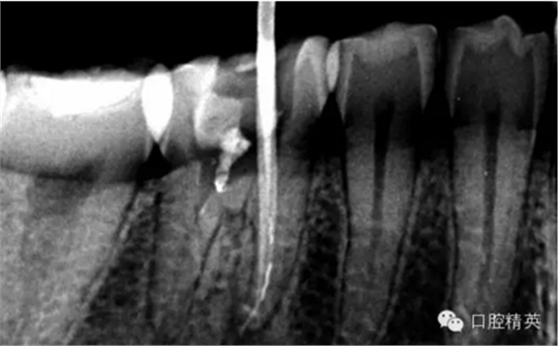

下面我來分享一下我近期的一個鈣化根管病例:

患者,肖某,男,32歲,#36慢性牙髓炎。遠(yuǎn)中舌根根尖1/3彎曲而且鈣化不通,我用盡辦法疏通了很久也沒到達(dá)WL,(我一直在幻想,要是有超聲系統(tǒng)該多好,可是現(xiàn)實很骨感,我們單位暫時還沒有超聲系統(tǒng)),后來我放棄了,最后的根充片顯示遠(yuǎn)中舌根充填物距根尖端2.84mm,屬于欠填范圍(根管內(nèi)充填物距根尖端2mm以上),其它三根根尖1/3鈣化相對沒那么嚴(yán)重,根充片顯示屬于恰填范圍(根管內(nèi)充填物距根尖端0.5~2mm)。歡迎網(wǎng)友們針對這個病例提出寶貴的建議!